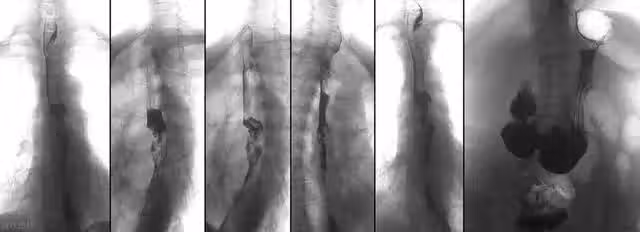

食道癌:很多人誤以為是咽炎!這 5 個症狀,提前逐一揭示